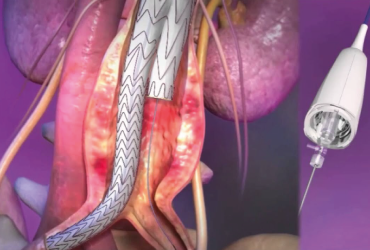

Unité d’exploration cardio-vasculaire et interventionnelle

au sein de notre centre de cardiologie, ce serait une équipe de cardiologues,...